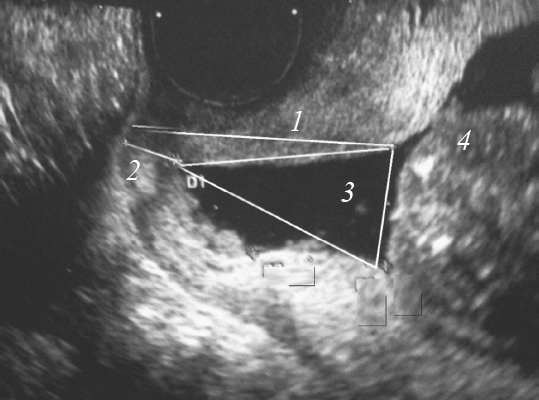

The rate of preterm birth remains high and has no downward trend, despite the introduction of new technologies. Isthmic-cervical insufficiency is one of the most important causes of premature birth. At the same time, many issues related to the prediction and treatment of isthmic-cervical insufficiency remain open. There is now a sufficient number of studies showing the relationship between somatotype, course and outcome of the disease. At the same time, stu dies related to the study of somatotypes in obstetric pathology are not enough.

The aim of the work is to assess the outcomes of pregnancy in women with isthmic-cervical insufficiency, taking into account the type of physique.

Materials and methods. the course and outcomes of pregnancy in 164 women with cervical insufficiency were studied. A computer somatotropina by R.N. Dorokhov all the best for measured strength of the pelvic floor muscles using a device pelvic muscle trainer.

Conclusions. The most frequently CI was found in women with mesosomatic and micro mesosomatic somatotype. Women macromesosomatic and micromesosomatic body types revealed low levels of muscle strength of the pelvic floor and a higher percentage of premature births. In groups macrosomy, macromesosomatic, microsomal body types often use different methods of correction CI. At the same time, the highest percentage of surgical correction of CI was observed in patients with macrosomatic type of physique. In other patients with different somatotypes, a non-surgical correction method was used.